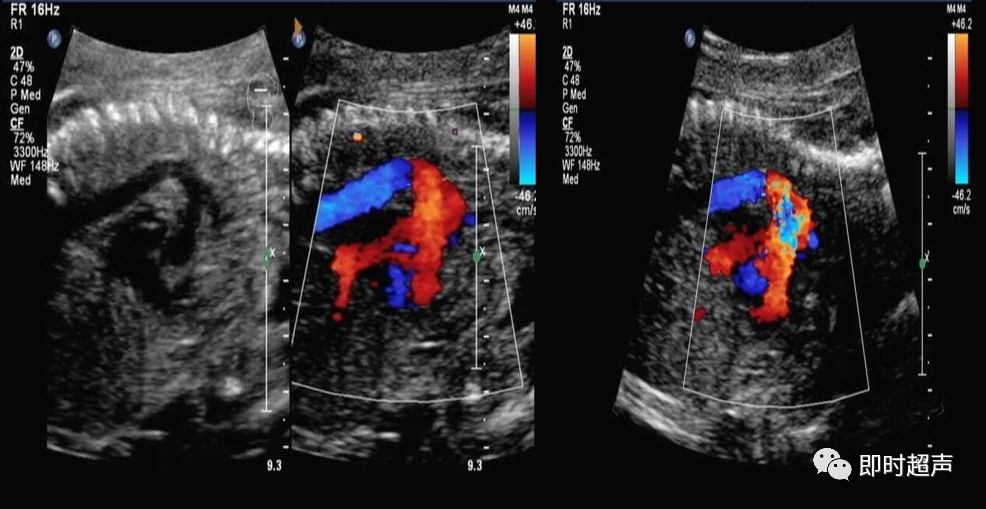

平行走形

肺动脉和主动脉平行走形

侧动探头连续观察即可观察到动脉导管走形迂曲,但还是汇入降主动脉

动脉导管瘤

胎儿动脉导管瘤的预后

- 动脉导管迂曲扩张和动脉导管瘤对新生儿最常见的影响就是动脉导管未闭。但随着研究的深入,发现动脉导管未闭的发生率并不是很高。

- 但有文献报道,少数动脉导管瘤会发生严重的并发症,甚至导致新生儿死亡。因此,如在产前发现动脉导管瘤或迂曲扩张,应提示临床并追踪。